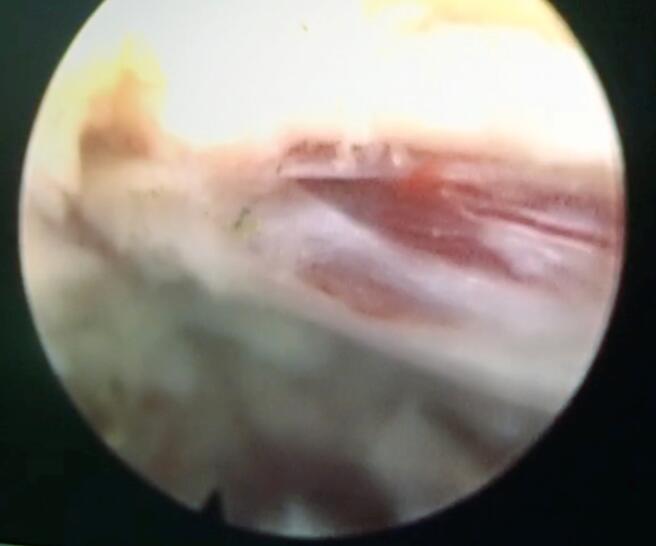

椎間孔鏡微創(chuàng)手術(shù)中

3月17日,唐師傅成功進(jìn)行了局麻下椎間孔鏡下L4/5椎間盤微創(chuàng)摘除術(shù)。手術(shù)過程中,唐師傅明顯感覺左下肢疼痛及麻木癥狀減輕,術(shù)后第二天,唐師傅在戴腰圍帶的情況下,就可以下床活動,并感覺雙腿行走有力,穩(wěn)健。

術(shù)中充露解壓神經(jīng)根